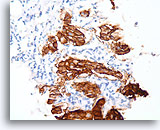

Papilloom, Borst FNA, Celblok.

Immunokleuring met p63 van de coupes van de patiënt in afbeelding 23-25 helpt de myoepitheliale cellen te markeren die door deze papilloom verstrooid zijn.

10X

Papilloom, Borst FNA, Celblok.

Immunokleuring met p63 van de coupes van de patiënt in afbeelding 23-25 helpt de myoepitheliale cellen te markeren die door deze papilloom verstrooid zijn.

10X

Papilloom, Borst FNA, Celblok.

De myoepitheliale cellen vormen nagenoeg continue rijen onder de ductale cellen (immunokleuring met p63).

40X

Papilloom, Borst FNA, Celblok.

De myoepitheliale cellen vormen nagenoeg continue rijen onder de ductale cellen (immunokleuring met p63).

40X